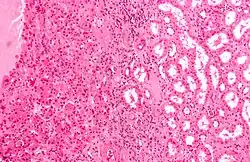

Oncocytes (left of image), as seen in a renal oncocytoma. H&E stain.

An oncocyte is an epithelial cell characterized by an excessive number of mitochondria, resulting in an abundant acidophilic, granular cytoplasm. Oncocytes can be benign or malignant.